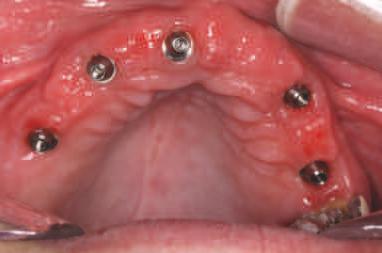

PREZENTARE CLINICĂ

O pac entă de 61 an s-a prezentat la Per odont cs/Per odontal Prosthes s Cl n c d n cadrul Un vers ty of Pennsylvan a School of Dental Med cne dor nd în pr nc pal să a bă „d nț f xaț ” în locul protezelor mob le ex stente (f g. 1). După f nal zarea unu examen stomatolog c cupr nzător, nclus v exam narea extra- ș ntraorală, evaluarea pr n tomograf e computer zată cu fasc cul con c (CBCT), fotograf erea dentară ș întocm rea f șelor dentare, s-a creat un plan pentru real zarea une reab l tăr full-mouth folos nd mplantur ș proteze dentare f xe. Pac enta purta proteze totale moble retenț onate pe m n - mplantur atât la mand bulă, cât ș la max lar. În t mpul evaluăr n ț ale, ea ș -a expr mat preocupăr le legate de estet ca restaurăr lor ex stente în ceea ce pr vește expunerea g ng vală ș

1. Imaginea intraorală a protezelor existente retenționate de miniimplanturi la prezentarea inițială.

2. Pacienta prezenta expunerea excesivă a componentei gingivale din protezele existente.

3. Situația pretratament mandibulară edentată cu cele patru mini-implanturi existente.